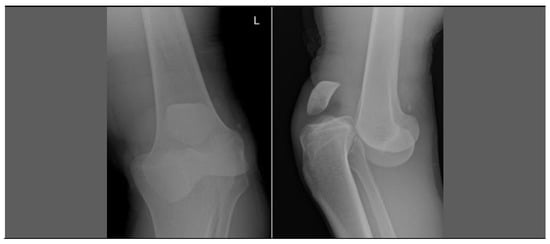

2.2. Second Case—Severity of Disease